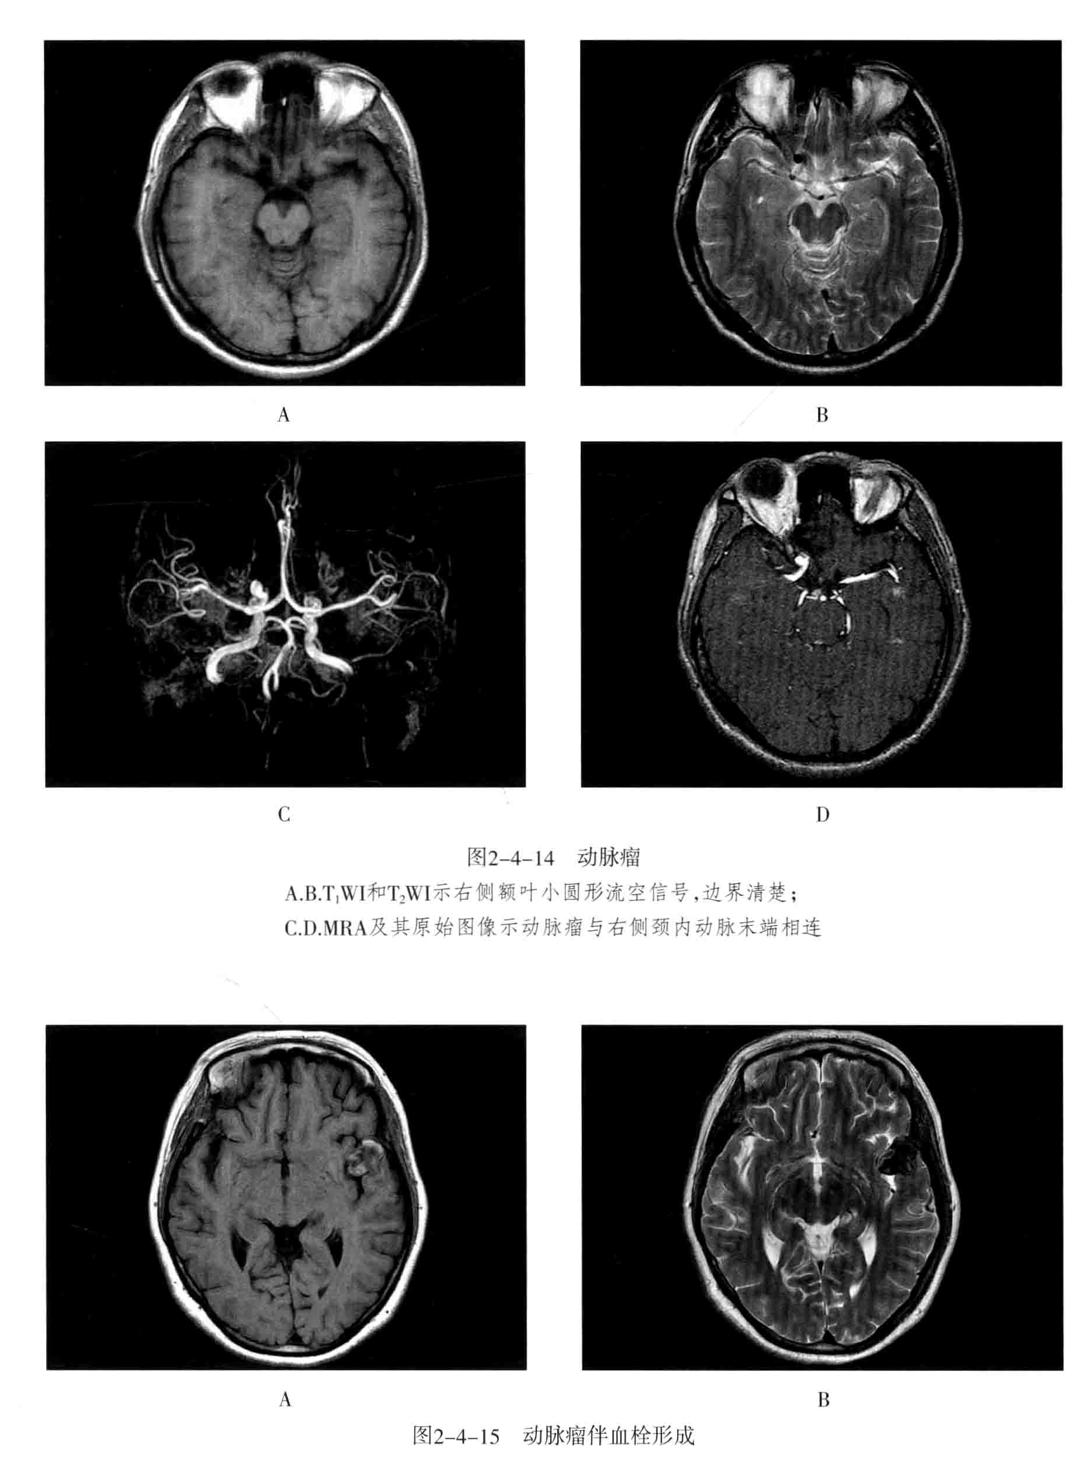

三、颅内动脉瘤

定义:颅内动脉局灶性异常扩大。

- CT平扫为圆形高密度影,边缘清楚、增强有均匀强化,CTA或MRA可明确显示动脉瘤及其与载瘤动脉的关系。瘤样凸起。

- 动脉瘤的瘤腔在T1WI、T2WI上均呈低信号,动脉瘤内有涡流时,也可产生轻微的不均质信号;瘤内血栓显示为高低相间的混杂信号。